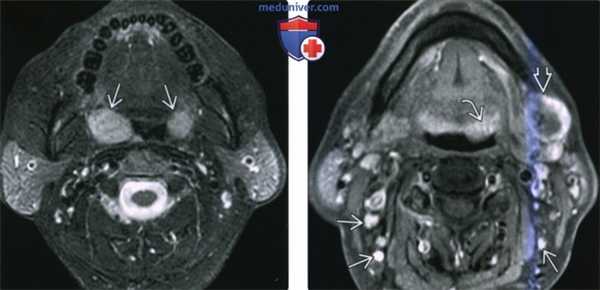

(Слева) MPT Т2ВИ FS в аксиальной проекции. В обеих небных миндалинах определяются мультифокальные лимфомы. Четкие края опухолей говорят о том, что они находятся в пределах капсул миндалин.

(Справа) MPT Т1ВИ FS с КУ, аксиальная проекция, этот же пациент. Определяется участок лимфомы в области лимфоидной ткани корня языка слева и крупный некротизированный лимфоузел IB уровня. На шее также визуализируются несколько мелких лимфоузлов, но установить, поражены ли они лимфомой, можно только при помощи метаболических исследований, например, ПЭТ/КТ.